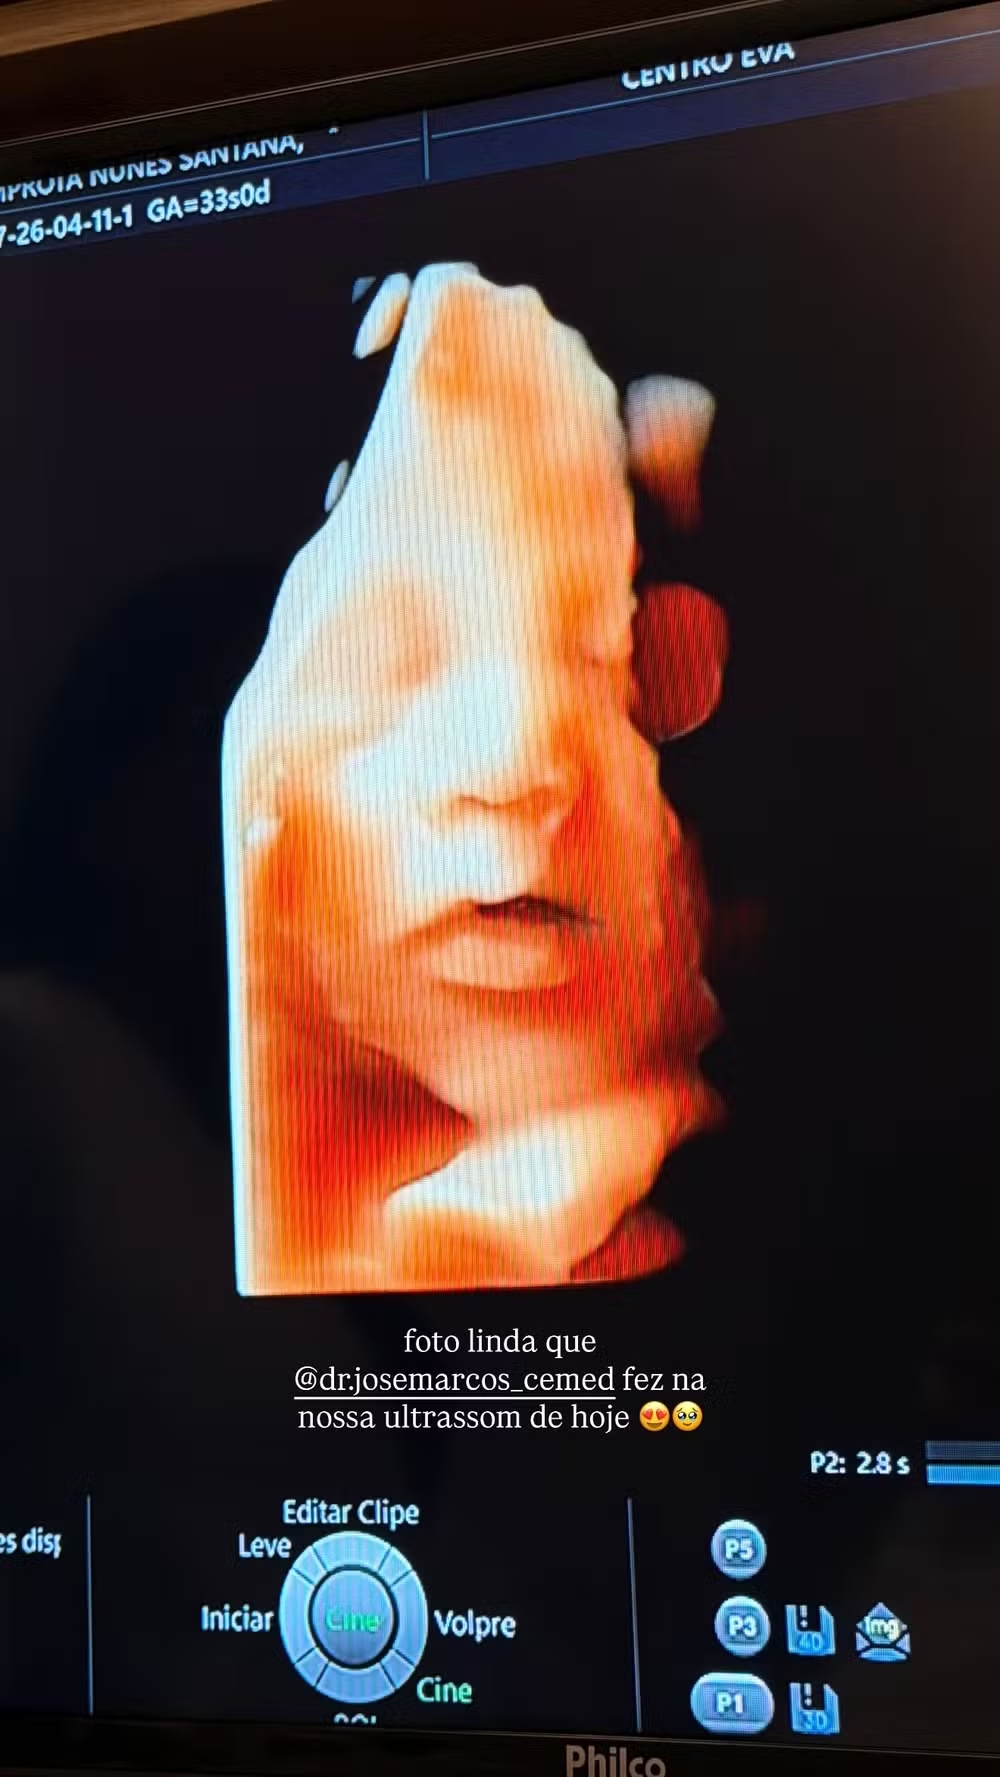

À espera do segundo filho, Lore Improta dividiu com os seguidores um momento especial da gestação. No último sábado (11), ela publicou nas redes sociais uma imagem do ultrassom e mostrou detalhes do rosto do bebê Levi, fruto do relacionamento com Léo Santana.

Já na reta final da gravidez, Lore se mostrou encantada com o registro e brincou ao comentar as características do filho.

“Nosso Levi está lindão e a cara de Liz e do papa Léo Santana, a mami não tem vez [risos]”, escreveu. Em seguida, elogiou o profissional responsável pelo exame: “Foto linda que o Dr. José Marcos fez na nossa ultrassom de hoje”.